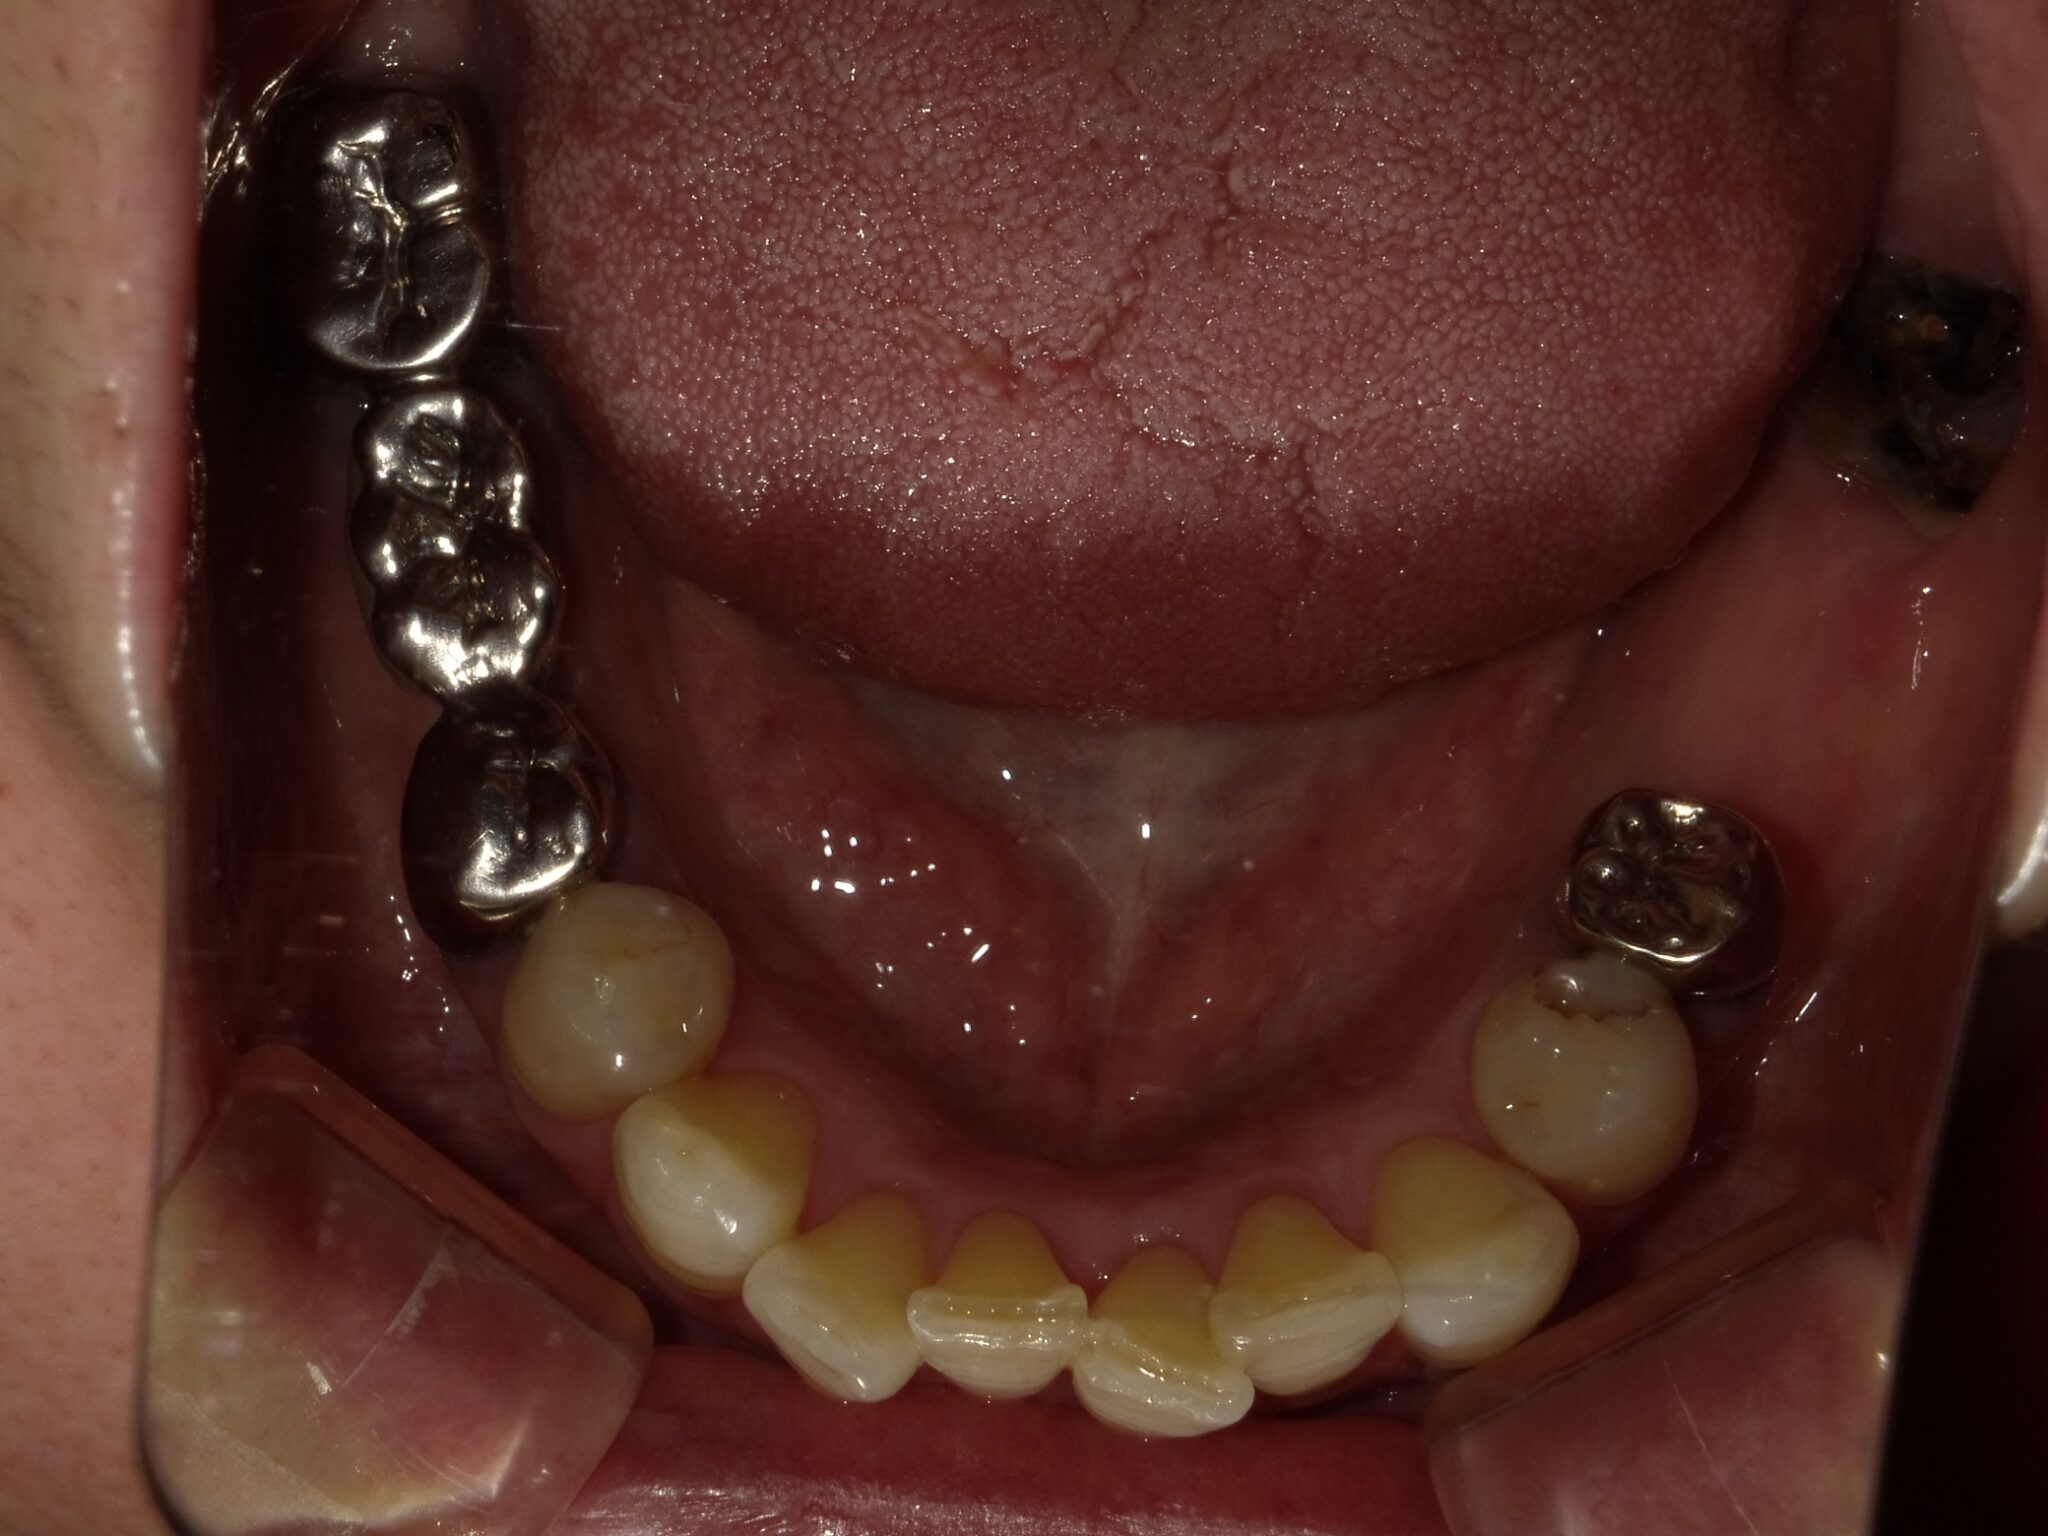

全顎治療症例

| 診断名・ 主な症状 |

臼歯部欠損 |

| 治療内容 | インプラント埋入(右上4・6,左上4・6,右下6,左下6) ジルコニアBr(右上3―左上3) ジルコニア(右下5,左下5) |